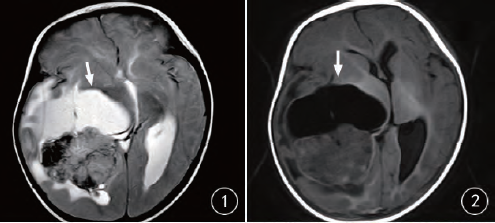

橫紋肌樣瘤是一種罕見的腫瘤,但生命綠洲卻憑借其獨特的醫(yī)療視角和先進的設備,走在治療的前沿,這里采用的治療技術(shù)不僅結(jié)合了傳統(tǒng)手術(shù)的優(yōu)勢,還融入了最新的生物技術(shù)、基因療法和免疫治療等前沿科技,經(jīng)驗豐富的醫(yī)療團隊緊跟國際醫(yī)學的最新進展,不斷嘗試將最新的研究成果應用到臨床實踐中。